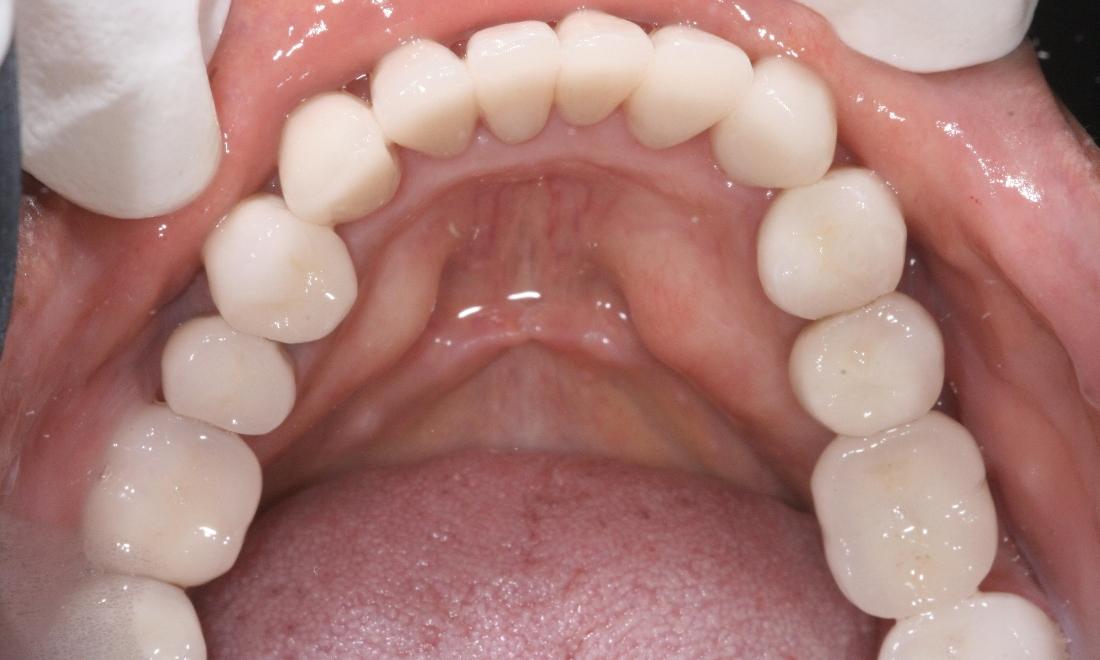

Above all, we are committed to offering and delivering exceptional, comprehensive dental care to each and every one of our clients. Through a unique mix of ultra-contemporary office design elements; the finest dental technologies, materials, and treatments; and a strong emphasis on exemplary customer service, it is our mission to create a practice environment which fosters the highest level of patient comfort safety, and overall satisfaction. We strive to protect the health of our patients and add beauty to their smiles. We will not be satisfied until we have perfected THE ultimate experience - one that includes Five Star service, extraordinary dentistry and makes a positive, lasting impression on the lives of our patients.